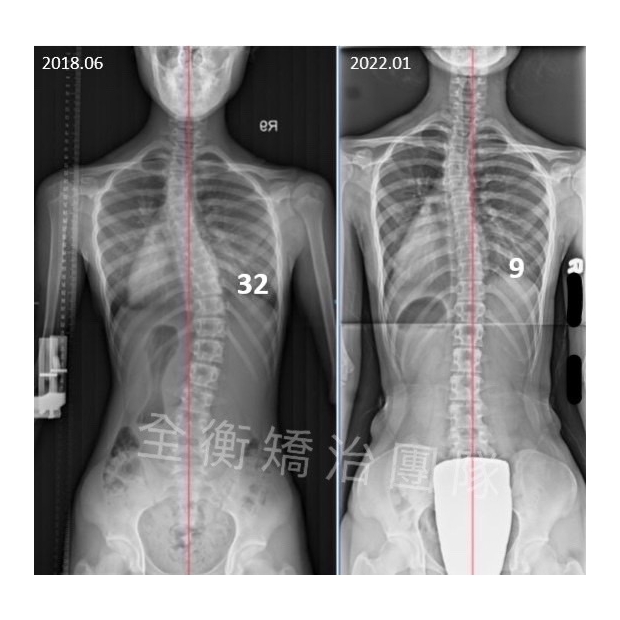

13嵗男生側彎矯治:每一度進步都凝聚著十分的努力 脊椎側彎矯正/脊椎側彎復健運動/早期發現,早期矯治13嵗男生側彎矯治:每一度進步都凝聚著十分的努力 脊椎側彎矯正/脊椎側彎復健運動/早期發現,早期矯治

脊椎側彎矯正 / 脊椎側彎復健運動

國二男孩 ,胸彎32度,腰彎18度

治療後胸彎24度,腰彎14度,體態改善顯著 -